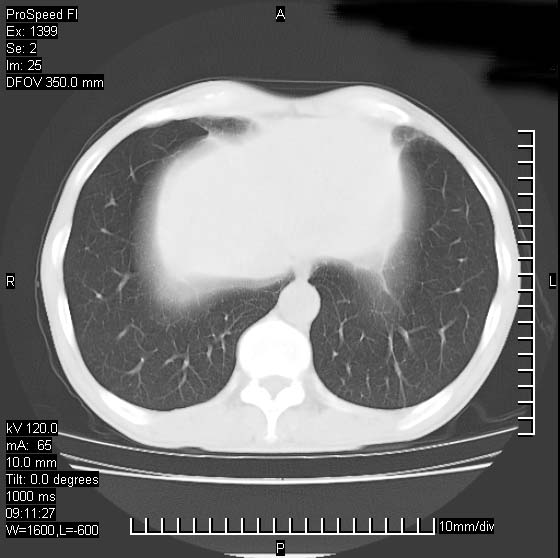

以下是引用卜一在2007-1-19 9:55:00的发言:[br]左肺沿胸膜下巨大肿块影,边缘呈分叶征,纵隔内见肿大淋巴结,右肺内另见一不规则结节影 .考虑:左肺周围性肺癌伴纵隔 右肺内转移.

以下是引用rgsyyf在2007-1-19 11:05:00的发言:[br]左肺上叶见形态不规则巨大软组织肿块影,边缘呈分叶征,纵隔内隆突下见肿大淋巴结,右肺内另见一不规则结节影 .考虑:左肺周围性肺癌伴纵隔即右肺内转移.